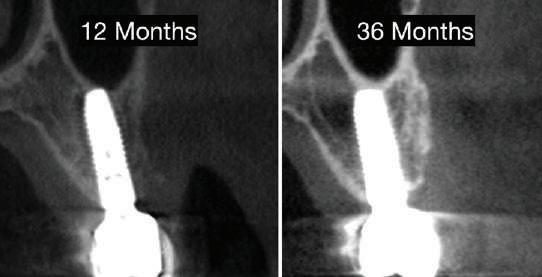

Scanarea intraorală finală și procedurile de restaurare au fost finalizate 3 luni mai târziu, iar implantul se afla în funcțiune de 36 luni la momentul redactării prezentului articol.